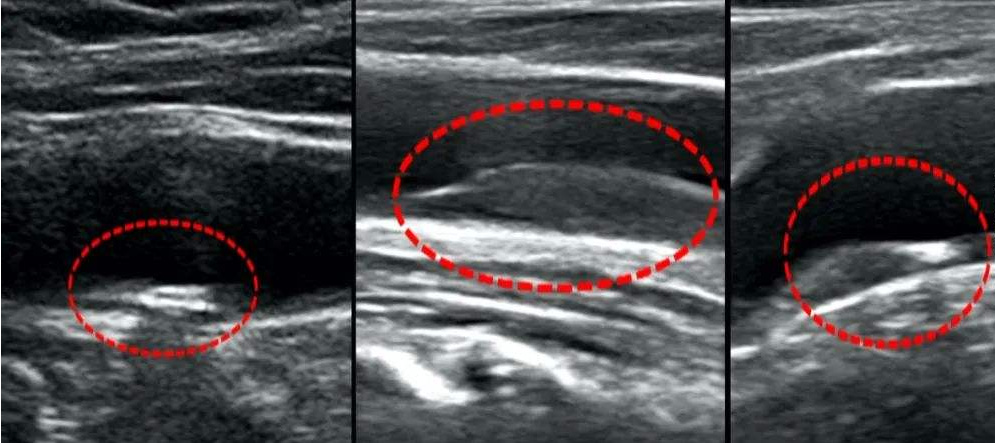

图像识别是深度学习等人工智能技术先突破的领域,已经广泛用于图片搜索、自动驾驶、人脸识别。而在医疗健康领域,目前看来医疗影像也会是人工智能与医疗结合中,比较可能先发展起来的领域。下面就以我公司研发的智能医疗影像系统为例,介绍下这个聚合了人工智能的智能医疗影像系统。

简单而言,医疗影像智能分析是指运用人工智能技术识别及分析医疗影像,帮助医生定位病症分析病情,辅助做出诊断。目前医疗数据中有超过9成来自医疗影像,这些数据大多要进行人工分析,如果能够运用算法自动分析影像,再将影像与其它病例记录进行对比,就能极大降低医学误诊,帮助做出准诊断。

1、主要是利用医疗影像检测、识别、筛查和分析技术,为医疗器械厂商和基层医疗提供影像识别服务,对新录入数据库的病例,它可以进行算法匹配,寻找出影像数据相似的案例;专注医疗影像分析应用,基于医疗影像定量分析,用数学模型和人工智能技术提高诊断准确性。